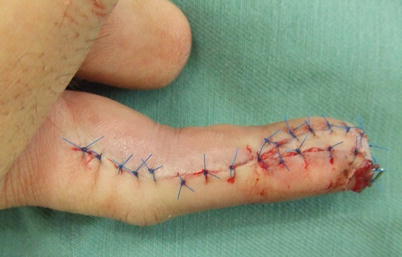

Fig. 8.8

Procedure 8: The tourniquet is released and the circulation of the blood flow is confirmed. The skin flap is rotated and advanced to distal to cover the finger tip. The skin flap is fixed in place using a Kirschner wire inserted into the fingertip. From this procedure, the neurovascular pedicle has been transferred from its original path to the volar center

Fig. 8.9

Procedure 9: The skin flap is sutured to the surrounding area

Fig. 8.10

Procedure 10: By rotating and transferring the flap, it is possible to form sufficient bulge in the volar fingertip. The incision line does not cross the DIP or PIP crease so there is no new scar contracture. (Part of photos reproduced from Hirase, Y.: Treatment of nail and fingertip injuries (6) using free flaps. MB Orthop 20:81–87, 2007)